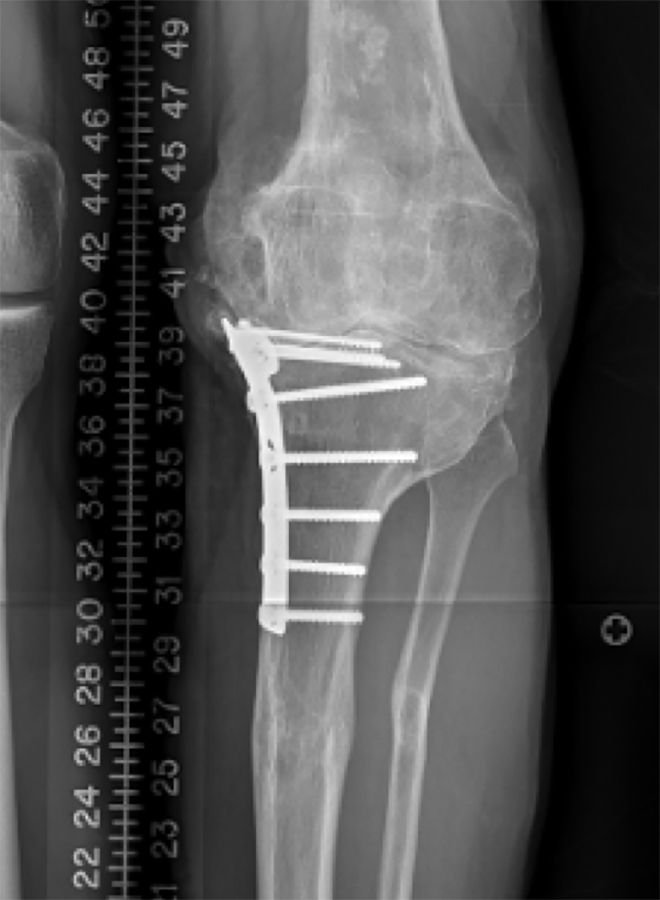

To make the decision, whether to correct the coronal deformity in a one stage or two stage fashion or to proceed with a primary total knee replacement the amount of angular deformity at the level of the knee provides the most reliable guidance. No matter where the extraarticular deformity is located doe the purpose of knee arthroplasty the overall mechanical deformity is measured as an angle between the mechanical axis of the femur (line through the center of the hip and the center of the distal femoral condyles) and the mechanical axis of the tibia (line through the center of the talus (ankle) and the center of the tibial plateau). A mechanical deformity in excess of 20-25 degrees usually suggests that a primary knee replacement without deformity correction is not possible. In these cases usually the deformity needs to be corrected first. For the correction of extraarticular deformities different options including correction over a nail, open osteotomy with plate fixation or external fixator exist. In my opinion the technique that interferes the least with the later total knee replacement should be favored. Open ostoeotomies and plate fixation should take into consideration the potential need for hardware removal at the time of surgery and plates should be placed medial along the standard medial parapatellar approach as often as possible. Correction using an intramedullary nail need to make sure that the nail does not extend into the bed of the primary knee implants and options for extramedullary alignment need to be available at the time of total knee arthroplasty (navigation, robotic or extramedullary alignment jigs) [3]. Finally, when using an external fixator, the risk of pin tract infection and osteomyelitis needs to be carefully weighed versus the ability for advanced 3-dimensional correction of the deformity. I personally had very good results with 2 stage correction using an external fixator or one stage correction using either an open plate fixation or intramedullary fixation using the stem of a revision femoral or tibial component. The later is especially appealing if the center of rotation and angulation (CORA) is close to the knee. Bony correction of the preexisting deformity renders the soft tissue balancing at the time of total knee replacement much easier and is usually indicated for less experienced surgeons. Rule of Thumb: For me a coronal deformity exceeding 25 degrees is an absolute and a deformity exceeding 20 degrees is a relative indication for a one stage or two stage correction of a preexisting extraarticular deformity (Figure 1a, b, c).

Often the first question is whether or not to remove preexisting hardware at the time of surgery or two-stage prior to knee replacement. Although there have been reports of positive cultures when evaluating removed hardware, I don’t think that prior hardware always needs to be removed before attempting a total knee replacement. Medial hardware on the proximal tibia or distal femur can usually be removed without difficulty through a standard medial parapatellar approach at the time of total knee replacement (Figure 6a, b).

I usually take a careful history of prior infections, open fracture and delayed wound healing after the initial open reduction and internal fixation. I have a low threshold to aspirate knees prior to implantation to exclude the remote possibility of a chronic infection or change my plan to a two-stage procedure if the removed hardware looks suspicious. An MRI imaging might help to detect evidence of osteomyelitis. In the presence of lateral hardware, I usually prefer to remove the hardware in a two-stage fashion. I don’t feel comfortable having a second incision around the knee at the time of a total knee replacement (Figure 7a, b).